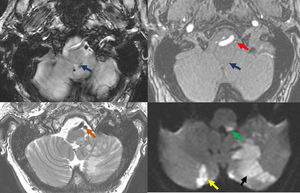

A) Estudio de resonancia magnética de cortes axiales. Técnica empleada, de izquierda a derecha y de superior a inferior: GRE, ARM TOF 3D, T2 FSE y DWI (b-valor 1.000). Hallazgos: infarto agudo con restricción de difusión en los territorios distales de la arteria cerebelosa posteroinferior (PICA) izquierda (flecha negra: hemisferio cerebeloso basal izquierdo y vermis ipsilateral inferior) y de ramas perforantes medulares (flecha verde: bulbo posterolateral). Foco isquémico agudo cerebeloso basal contralateral (flecha amarilla). Se muestra la ausencia de flujo por trombosis en el segmento V4 de la arteria vertebral izquierda (flecha roja) y PICA izquierda (flecha azul: se señalan sus segmentos: medular, posterior y supratonsilar). Nótese la diferencia de señal respecto a segmento V4 derecho en eco de gradiente y en 3D TOF. En T2 falsa imagen de luz permeable (flecha naranja: hiposeñal en la arteria durante T2, debido al carácter agudo del trombo). B) Reconstrucción MIP de estudio RM 3D T1 + RM con gadolinio de TSA (lados derecho e izquierdo). Hallazgos: disección de la arteria vertebral izquierda en el segmento V2. Izquierda: angiografía por RM (ARM) muestra afilamiento oclusivo en segmento V2 de la arteria vertebral izquierda, característico de DAV (flecha naranja). La arteria vertebral derecha es permeable (flecha azul). Derecha superior: RM Axial T1 FS muestra hiperseñal periférica en la pared vascular de AV izquierda nivel V2-V3 representando un hematoma intramural (flecha amarilla). Derecha inferior: RM Axial T2 muestra ausencia de vacío de señal en AV izquierda nivel V2-V3 (flecha roja), la derecha sí muestra el vacío de señal normal (flecha verde).